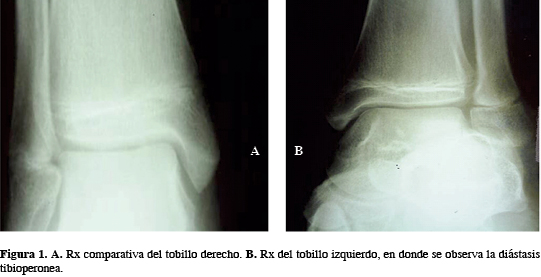

A la exploración clínica, llama la atención el dolor intenso a la palpación sobre la sindesmosis del tobillo. En la Rx simple se observa una apertura de la sindesmosis, por lo que se solicita Rx del tobillo sano para comparar; una vez hecha la comparación y fortaleciendo el diagnóstico de diástasis de la mortaja del tobillo (Figura 1), se solicitaron TC, en donde se pudo corroborar la lesión (Figura 2)